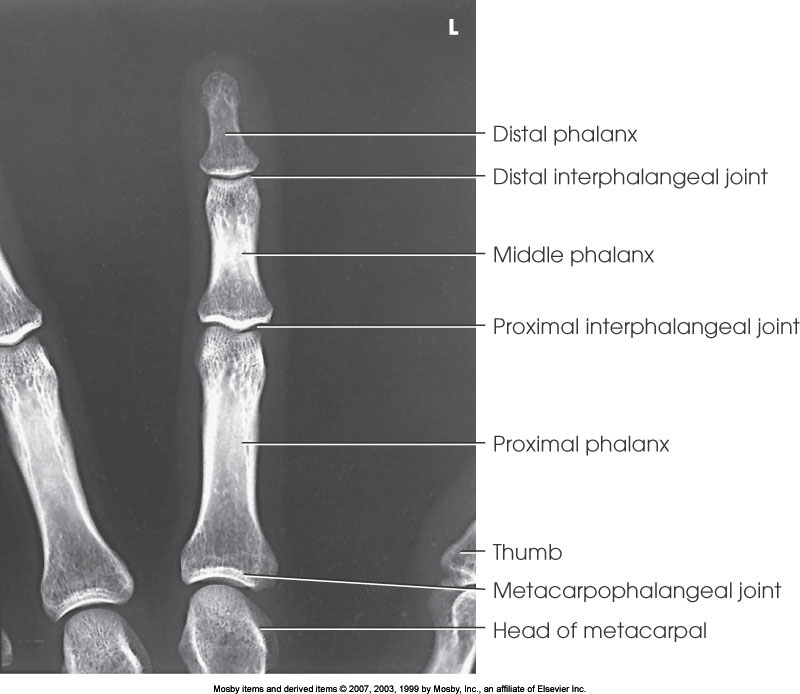

PA Finger

What position is demonstrated?